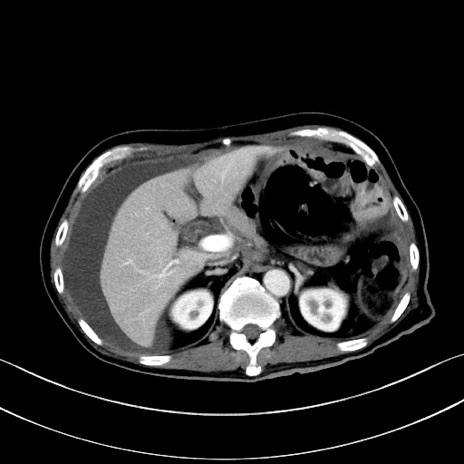

症例28(横断像)

【症例】60歳代男性

【主訴】嘔吐

【現病歴】胃癌にて胃全摘後。食思不振が悪化し、夜中に嘔吐することがある。

【既往歴】胃癌、胃全摘、脾摘、胆摘後

【データ】WBC 5900、CRP 10.56